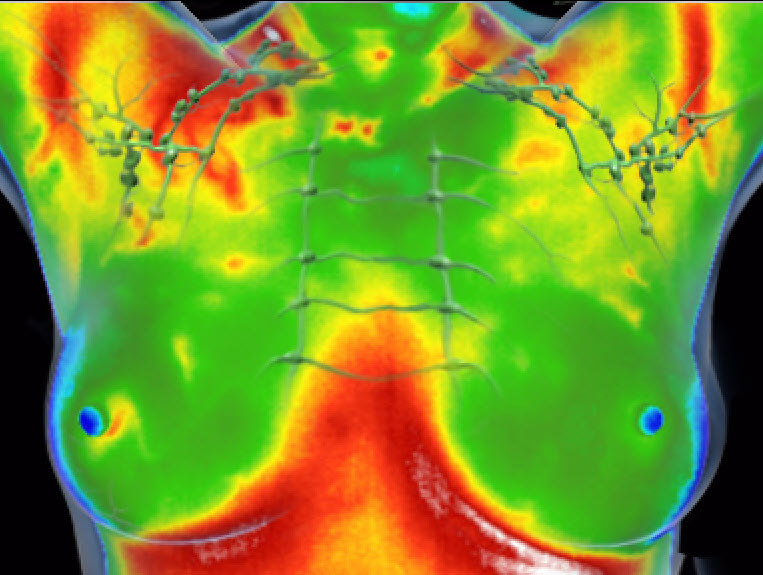

Under en termografiundersökning tas bilder med en värmekänsliga kamera. Undersökningen är helt smärtfri och involverar ingen beröring.

Termografi upptäcker minimala temperaturförändringar, vilket ger extremt detaljerad information för tidig upptäckt av förändringar.

En stor fördel med termografi är dess användning av infraröd teknik, vilket innebär att det inte finns någon strålningsrisk förknippad med undersökningen. Många traditionella metoder för bröstscreening, såsom mammografi, innebär exponering för strålning, vilket kan innebära risker vid frekvent användning. Termografi erbjuder en icke-invasiv, strålningsfri lösning som gör det möjligt att utföra regelbundna kontroller utan att oroa sig för de potentiella biverkningarna av strålning. Det gör termografi till ett mycket bra komplement till rådande screeningmetod – mammografi.

När du kommer till oss får komma in i vårt undersökningsrum där du sitter med bar överkropp framför vår värmekänsliga kamera. För att hitta en stabil temperatur kan vi behöva använda en fläkt under några minuter. När temperaturen är stabil tar vi 5 bilder i olika vinklar. Därefter får du klä på dig och så går vi igenom bilderna tillsammans. Avslutningsvis får du med dig råd om kost och livsstil tillsammans med råd om hur du kan ta hand om din brösthälsa baserat på det vi sett på bilderna.